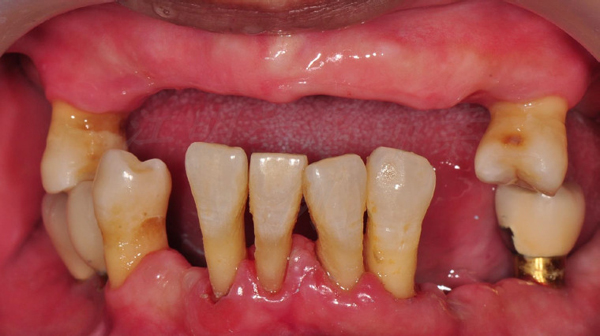

治療前